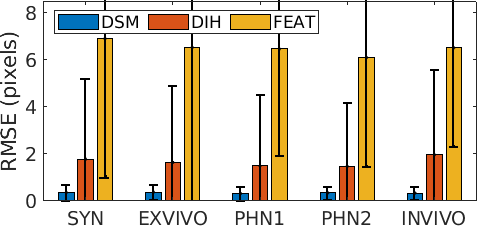

We perform comparison of DSM with a feature-based (FEAT) [2] and DIH [4] methods. FEAT extract SURF features from a pair of images and performs an exhaustive search for feature matching to estimate the homography. We report the mean residual error (as detailed in [11]) between the GT and estimated relative homographies for SYN (the only sequence with known GT homographies). For quantitative evaluation, we report the average Root Mean Square Error (RMSE) between pair of image patches with known GT homograpies obtained from data augmentation, and average pixel-wise photometric error computed by taking the L1-distance between frame Fk+1 and reprojected Fk using the estimated homography. We also report qualitative results through visualization.

The visualization and comparison results on one circular loop (360 frames) of the SYN sequence are shown in Fig. 3(a)-(c). Note the small drift in DSM compared to FEAT. Similar behavior is observed from the mean residual error in Fig. 3(d) where the errors are reported for FEAT, DIH and DSM for the complete length of the sequence (811 frames). It can be seen that the error for FEAT starts increasing after approximately 300 frames and the mosaic starts drifting away. DIH error explodes within a few frames due to the random perturbation during training (Sec. 2). On the other hand, the error for DSM is very small and remains bounded. This is further verified from the low RMSE (0.36) and photometric (2.48) errors for DSM (Fig. 4). Comparison of our proposed DSM with FEAT and DIH is presented in Fig. 4. Overall the pairwise homography errors are high for FEAT for all five sequences due to poor visual quality and lack of texture in the fetoscopic videos. The RMSE and photometric errors for DIH are low compared to FEAT but are always higher compared to DSM (e.g. RMSE on EX for DIH (1.64) and DSM (0.38)). In DIH, this error accumulated over time during mosaic generation and resulted in a large drift. For EX, PHN1, PHN2 and INVI sequences, the average RMSE errors are 0.38, 0.32, 0.35 and 0.34, and photometric errors are 0.98, 1.76, 1.52, 2.42, respectively.